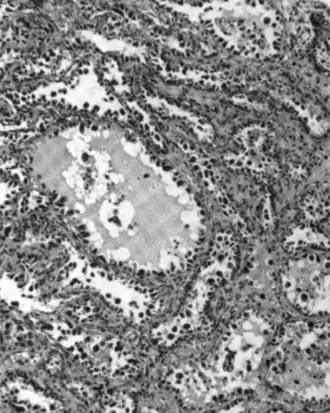

Mucinous tumors include mucinous adenocarcinoma and mucinous cystadenocarcinoma.[29]

Mucinous adenocarcinoma

Mucinous adenocarcinomas make up 5–10% of epithelial ovarian cancers. Histologically, they are similar to intestinal or cervical adenocarcinomas and are often actually metastases of appendiceal or colon cancers. Advanced mucinous adenocarcinomas have a poor prognosis, generally worse than serous tumors, and are often resistant to platinum chemotherapy, though they are rare.[29]